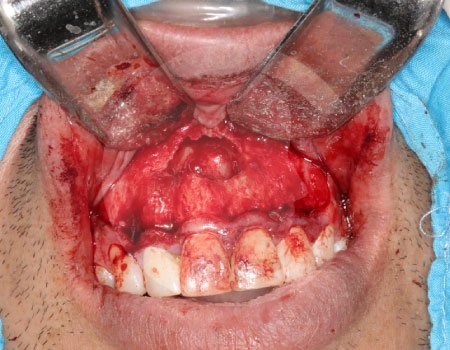

Un absceso es una acumulación de infección que puede causar dolor intenso e inflamación. Cuando el proceso infeccioso no mejora con tratamiento convencional, puede ser necesario realizar un drenaje o manejo quirúrgico.

Es una conexión entre la cavidad oral y el seno maxilar que puede ocurrir tras extracciones o infecciones. Su tratamiento busca cerrar adecuadamente la comunicación para evitar molestias e infecciones sinusales.

El tratamiento depende del origen y gravedad de la infección. Puede incluir medicamentos, drenaje quirúrgico o procedimientos específicos para eliminar el foco infeccioso y evitar complicaciones.

En casos de mayor complicación deberá ser ingresado a cuidados hospitalarios, y programar el procedimiento quirúrgico que corresponda